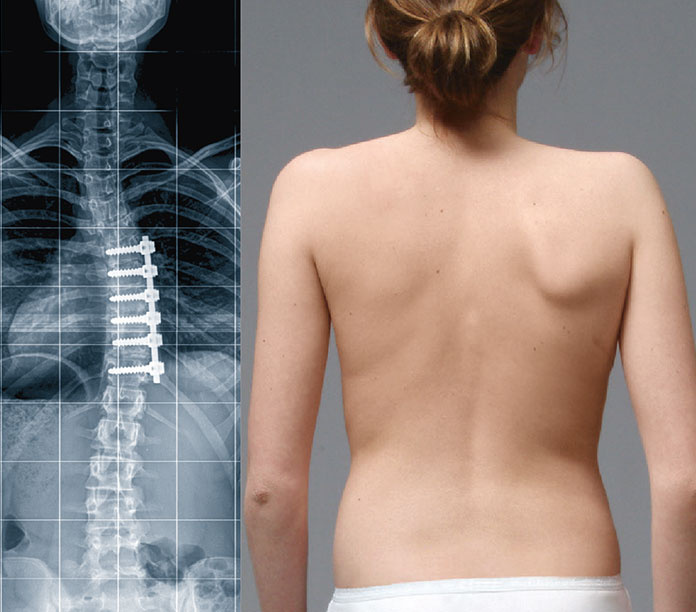

Bei einer Skoliose-OP wird die Wirbelsäule mit Metallimplantaten üblicherweise mit Schrauben-Stab-Systemen korrigiert und lebenslang in korrigierter Stellung stabilisiert. Wenn bei Ihnen Skoliose diagnostiziert wird werden Sie wahrscheinlich keine Operation benötigen. Der Chirurg darf dabei keine Nerven des Rückenmarks oder andere wichtige Strukturen verletzen.

Durch eine Skoliose-Operation kann die Krümmung deutlich verbessert werden. Hierzu empfiehlt sich bei Skoliosen ab 20 Grad die Orthesenversorgung und ab 45 Grad eine Operation. Bei einer Skoliose im Erwachsenenalter gibt es je nach Ausprägung eine Reihe von Therapien die je nach Ausprägung eingesetzt werden. Dazu ist es notwendig bestimmte Wirbelsäulensegmente zu versteifen Spondylodese um künftig eine volle Belastbarkeit zu ermöglichen. Bei einer Skoliose-OP wird die Wirbelsäule mit Metallimplantaten üblicherweise mit Schrauben-Stab-Systemen korrigiert und lebenslang in korrigierter Stellung stabilisiert. Dies ist eine Krümmung in der Wirbelsäule die durch die Verschlechterung in den Gelenken derselben verursacht wird. Wie wird eine Skoliose bei Erwachsenen behandelt. Bei dieser Wirbelsäulen-OP muss der versteifte und veränderte Wirbelsäulenabschnitt unter Vollnarkose entfernt werden. Operation der Wirbelsäule bei Skoliose Die operative Behebung der Skoliose ist ein gravierender Eingriff.